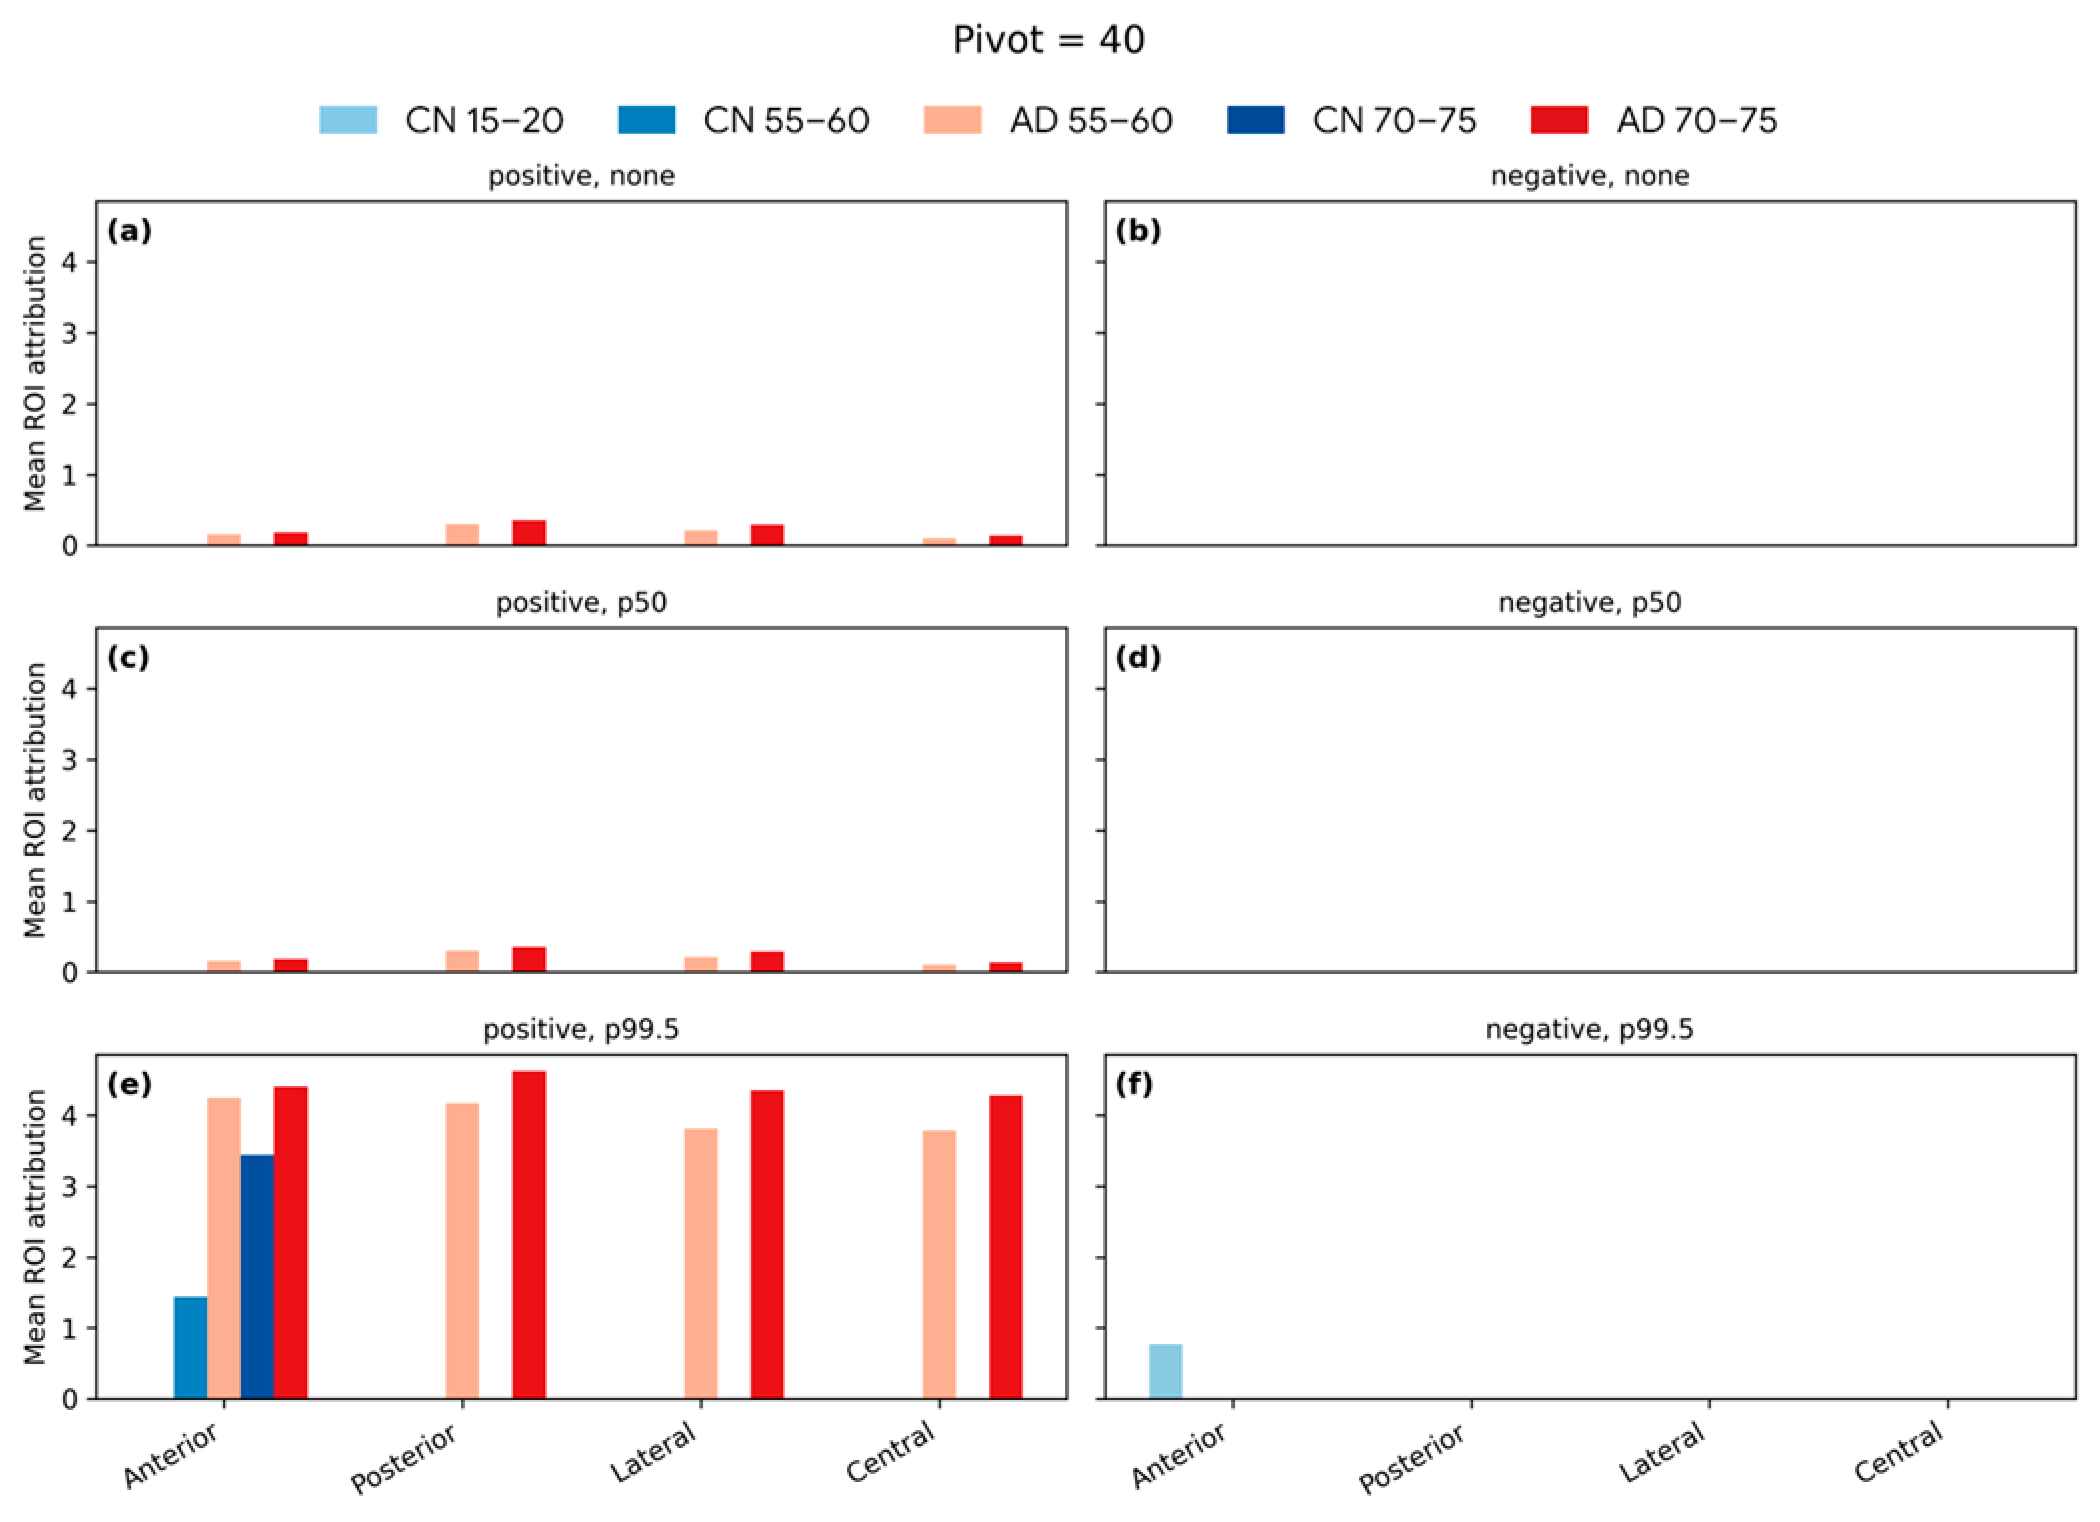

4.6. Softmax-Derived Brain Age Mapping Analysis